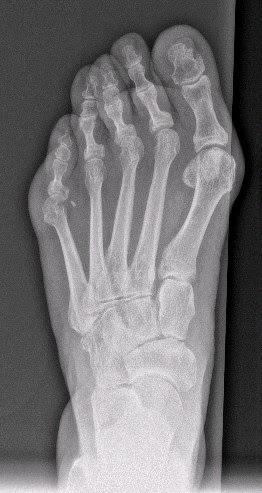

Para ello opté por la realización de una osteotomía (corte en el hueso) de los metatarsianos, fijados el primero con un clavo-tornillo específicamente diseñado para ello y el quinto con 2 tornillos de rosca ocultable para evitar roces innecesarios.

Estas técnicas a su vez se realizan mediante cirugía de mínima incisión, siendo el postoperatorio mucho más satisfactorio para el paciente.El resultado lo considero espectacular, no solo en la corrección de la deformidad, sino también en la obtención de un estrechamiento tranversal del pie de unos 2 cm (casi un 20% de su anchura), por lo que la paciente está ahora calzando zapatos normales sin ningun problema, cuando antes era imposible.Las radiografías de antes y después: